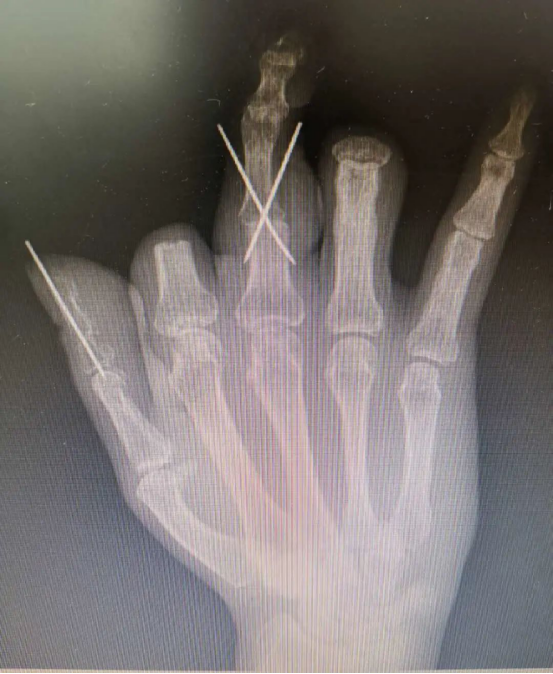

患者陳先生在工廠上班時不慎被沖床沖壓右手,被送到醫院時,整只手血肉模糊,肌腱、血管外露。診斷結果為4指毀損離斷傷,已經無法直接再植,需要“切腳趾、補手指”。

“缺多少、補多少,缺多少、切多少,對于再造手術,我們在關注創面修復的同時,也需要對供區進行關注。不光要注重改善手部功能,還要盡可能減少足部供區的損傷。”主刀醫生胡明興說,考慮到患者對術后恢復效果預期高,經過與患者及家屬溝通,科室團隊決定利用3D打印技術,通過數字化精準設計,輔助手指再造。

在放射科的支持下,醫院對患者雙手進行了CT三維重建,通過技術處理,虛擬出了患者缺失的手指,再使用新型材料打印出3D模型,模擬患者的斷指。通過對3D模型進行設計取樣,對患者右拇指、中指精準再造。

手術過程順利,由于3D打印技術的精準化輔助,兩根再造的手指外形美觀,不需要進行二期整形修復,足部供區創傷也達到最小化。又能用右手寫字、吃飯,陳先生很高興,“等這兩根手指恢復得差不多了,我馬上就來修復剩下兩根手指!”